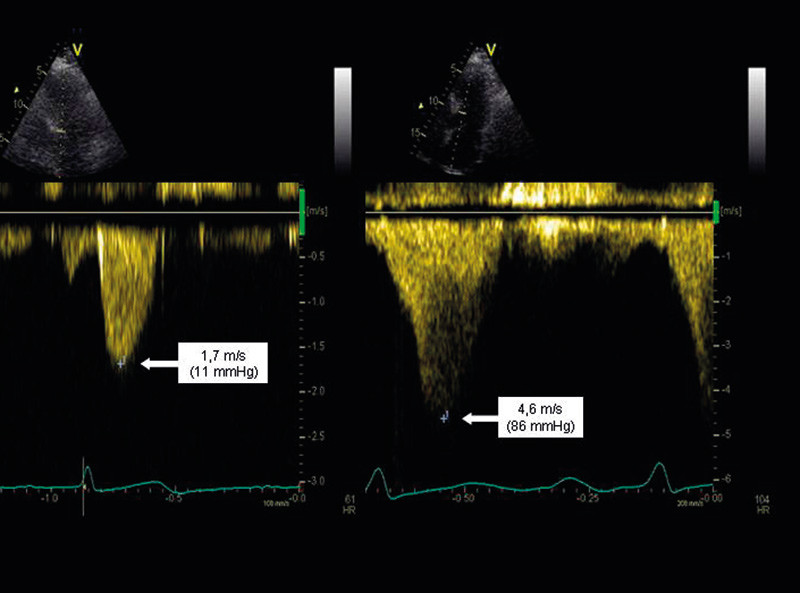

The obstruction of the outflow tract may cause the anterior leaflet of the mitral valve to be drawn forward during the systole and causes the so-called SAM (systolic anterior movement) phenomenon. This could result in an obstruction of the outflow tract, and a significant mitral insufficiency may occur. The blood flow from this mitral insufficiency may be located close to the blood flow in the outflow tract, so that distinguishing between them may be difficult. Often, parts of both velocity signals are included in the same registration. However, they can be distinguished by the fact that the blood flow in the mitral insufficiency starts earlier than the blood flow through the outflow tract, and because the obstruction produces a late-systolic, powerful acceleration of the blood-flow velocity, with a characteristic, knife-shaped signal (Figure 2).

Figure 2.  A patient with hypertrophic obstructive cardiomyopathy. Echocardiography with continuous Doppler registration of…

Figure 2. A patient with hypertrophic obstructive cardiomyopathy. Echocardiography with continuous Doppler registration of the outflow from the left ventricle. Recording at rest (left) and during exercise with a supine bicycle (80 W) (right). The two images have different scales for time and velocity. The figure shows the maximum blood-flow velocity and estimated pressure drop in the outflow from the left ventricle (the pressure drop is equal to the square of the velocity multiplied by 4). The estimated pressure drop increased from 11 mmHg at rest to 86 mmHg during physical exercise, which is consistent with a stress-induced increase in the outflow obstruction.